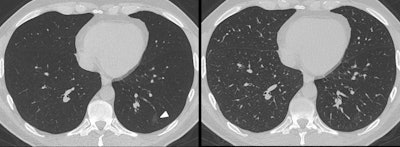

Minimum intensity projection (MinIP) reconstructions improve the accuracy of chest CT exams when it comes to identifying ground-glass opacity (GGO) in patients with suspected COVID-19 disease, according to a study published December 14 in the European Journal of Radiology.

As MinIP has been shown to have a higher accuracy for assessing GGO in comparison with standard MPRs in interstitial lung disease, Booz and colleagues sought to investigate whether it could improve CT's performance in patients with suspected COVID-19.

Of the 185 patients, 149 (80.5%) had chest CT scans that showed ground-glass opacity. Images processed with MinIP showed higher sensitivity, specificity, and accuracy for evaluating GGO compared with standard MPR series, the group wrote.